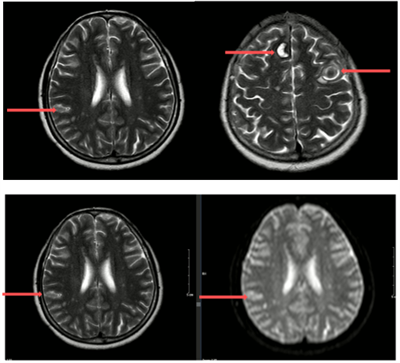

CASE LÂM SÀNG ĐIỀU TRỊ MIỄN DỊCH UNG THƯ PHỔI DI CĂN NÃO TẠI BỆNH VIỆN BẠCH MAI Ngày đăng: 28/01/2026 Ung thư phổi là một trong những bệnh ung thư thường gặp nhất. Tại Việt Nam, theo số liệu GLOBOCAN 2022, các số liệu cho thấy ung thư phổi đứng hàng thứ ba về tỉ lệ mới mắc và thứ hai về tỷ lệ tử...

Điều trị ung thư phổi di căn não tại Trung tâm Y học hạt nhân và Ung bướu - Bệnh viện Bạch Mai Ngày đăng: 28/01/2026 Theo GLOBOCAN 2022, ung thư phổi là một trong những nguyên nhân hàng đầu gây tử vong do ung thư trên toàn cầu. Tại Việt Nam, ung thư phổi có tỷ lệ tử vong cao đứng thứ 2, chỉ sau ung thư gan. Phần...